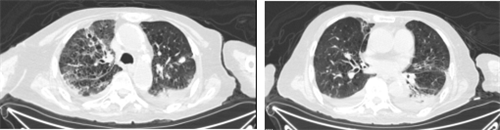

患者常先生因“间断呕吐1周,伴发热4天”来我院呼吸科就诊。入院前4天,患者病情迅速进展,体温最高达39℃,一般状况差,喘息症状加重,行胸部CT示右肺及左肺上叶大片实变、斑片、索条及磨玻璃密度影(见图1),入院后急查动脉血气提示I型呼吸衰竭,低氧血症,鼻导管吸氧流量5L/min,末梢氧合波动在85%-88%,患者体温持续在39.5℃以上,B型钠尿肽2399.6pg/ml,尿素氮19.85mmol/L,肌酐187umol/L。结合该患者的症状、体征、影像学及实验室检查,考虑为重症肺炎、呼吸衰竭、急性心力衰竭、肾功能不全。

图1胸部CT(2022.03.01)